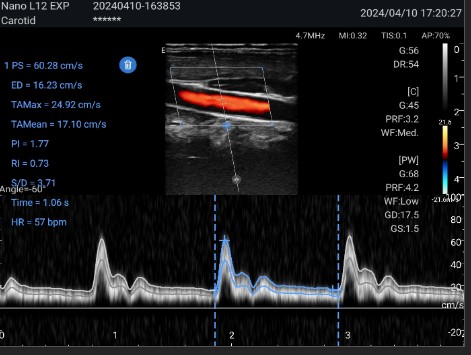

Available with linear probe Linear - high frequency, lower penetration, high resolution (ideal for superficial structures and fine details such as vessels, thyroid, breast, testicle, etc.).

Range Frequency: 4–12 MHz

Features - Ultraportable Nano L12 EXP EDAN ultrasound scanner with linear probe

Auto B-Line and Fast/eFast: Fast navigation protocol for lung condition assessment and emergency diagnosis.